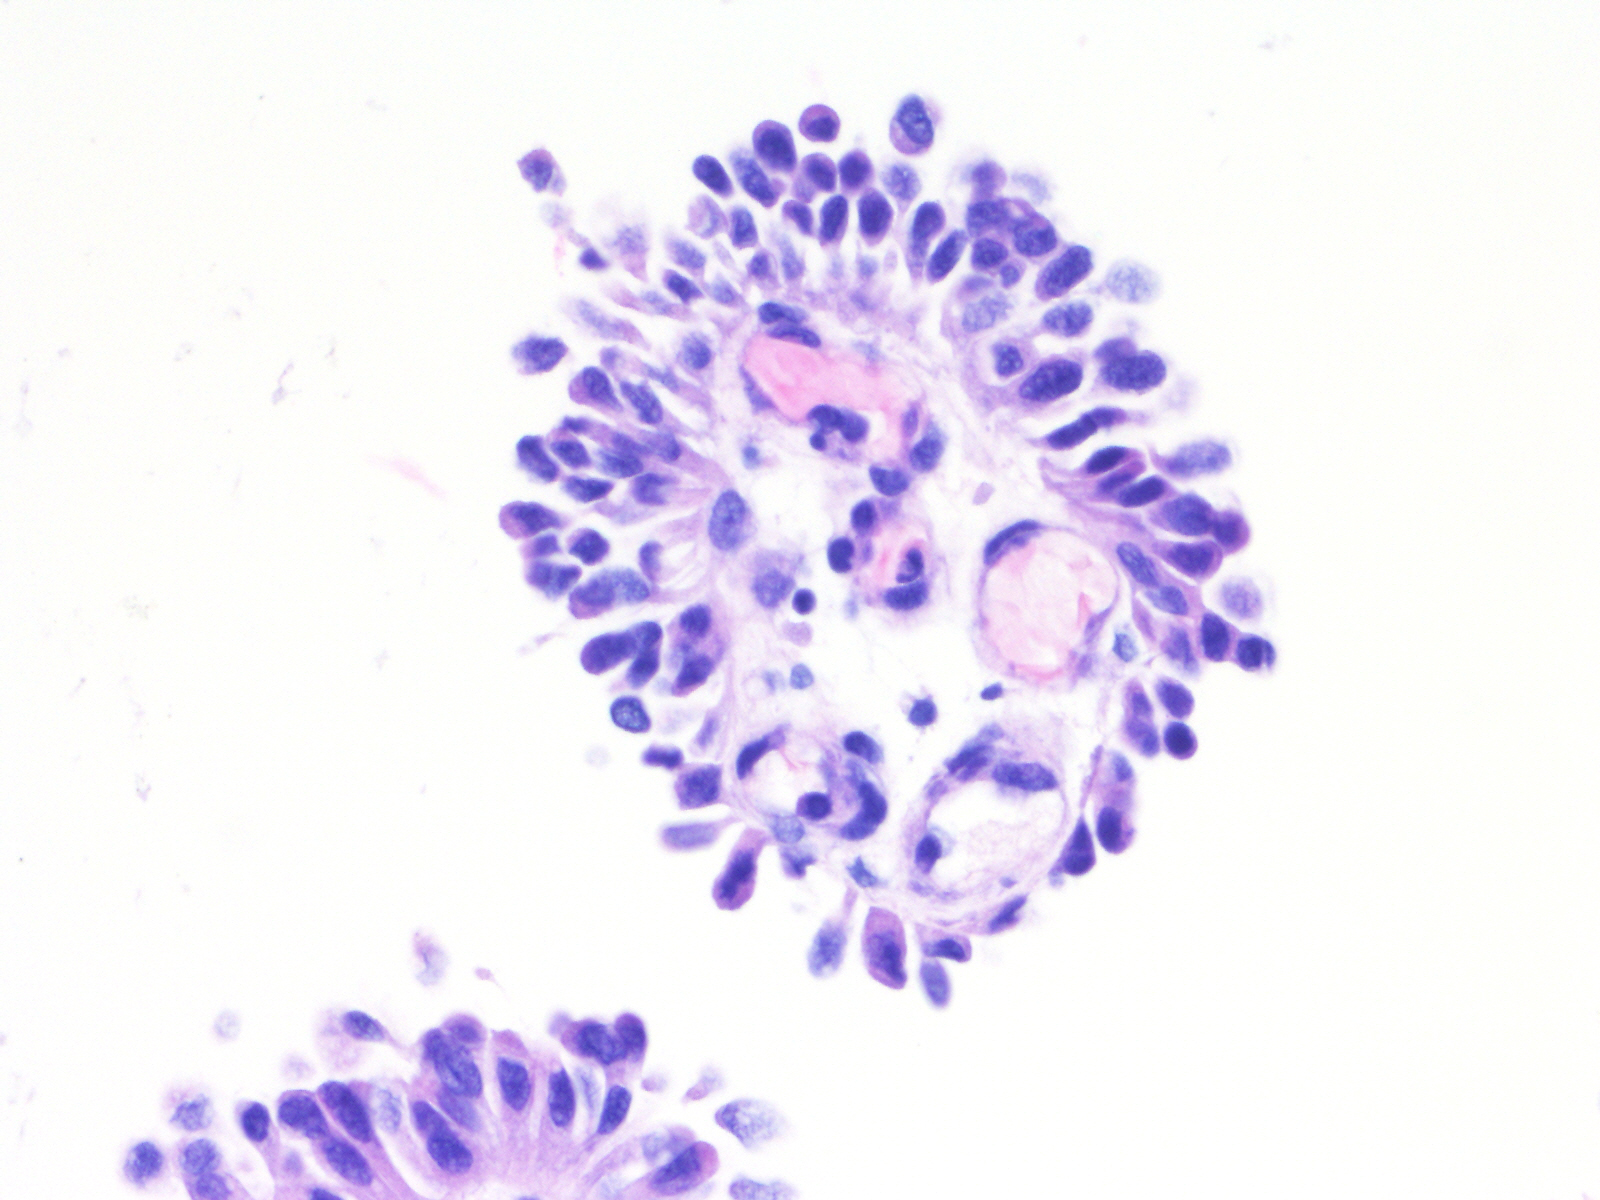

Bladder Papillary Lesions

Case ID: 543